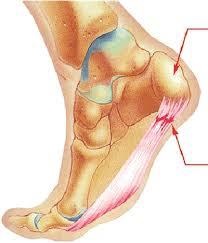

Fara nici factori traumatici durere pot să apară în articulația umărului, șoldului și călcâi. senzația neplăcută însoțește o persoană atunci când mersul pe jos, uneori, nu permițându-i să se miște mai departe. Când te duci la spital și spune că aveți o durere în călcâi, odată ce auzi diagnosticul de „fasciita plantara“, sună în versiunea internă ca „pinten toc“. Astfel de fasciita pot fi în orice parte a corpului în cazul în care tendoanele conecta oasele. Dacă se îngropa în anatomia și căutați cauza aceasta, atunci ai nevoie pentru a începe cu faptul că piciorul are un set care ne permite să meargă cu ușurință. El ajută tendoanele și mușchii noștri rămân puternice. De-a lungul întregului tract tendonul piciorului (fascia) trece prin partea de jos a călcâiului și oasele lungi. Dacă o persoană are picioare plat, atunci un astfel de set de aceasta nu are, iar fascia este constant în tensiune. Situația etalonat apare la cea mai mică exercitarea, la o greutate în exces, necorespunzătoare atunci când alegeți încălțăminte.

Fasciita Periodic lacrimă de fibre, astfel se concentreze excitație, cauzand dureri severe în călcâi. Toate tendoanele, ligamentele și oasele - este țesutul conjunctiv, este în toate articulațiile și coloana vertebrală. Dacă o persoană este de multe ori o durere în călcâi, atunci sondajul complet poate fi găsit și alte manifestări de boli ale țesutului conjunctiv, cum ar fi hernie sau osteocondrozei. Pentru funcționarea normală a țesutului este necesară pentru a corecta o dieta echilibrata, aportul zilnic de standarde de apă, fibrelor de colagen și elastină. Firește, atunci când există durere în orice parte a corpului, o persoană care dorește să obțină rapid scăpa de ea și tratează manifestările locale, mai degraba decat uita la cauza rădăcină. Dar, dacă suferiți de dureri severe în călcâi, nu loțiuni, masaje, și operarea nu va ajuta. Abandonați aceste proceduri nu sunt necesare, ele sunt chiar dimpotrivă, va fi util, dar dacă nu avea grijă de refacerea țesutului conjunctiv, timpul va fi pierdut în zadar.

În plus față de cele de mai sus: puteți cumpăra tălpi interioare speciale în pantofi cu inserții detașabile. Branțul are o gaură în care va cădea pe lobul piciorului (lobul constă din săruri de calciu, care sunt depozitate la fascia plantară). durere Heel la mers imediat redus. Este logic că o astfel de branț poate fi făcută, și el însuși, pentru acest lucru în burete trebuie să taie o gaură mică.